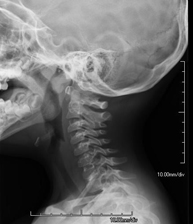

Tècnica que usa els raigs X a través de la qual s'obtenen imatges del càvum per al seu estudi. Indicacions: dificultat respiratòria, angines de repetició en lactants i nens - RX Columna cervical

Tècnica que usa els raigs X a través de la qual s'obtenen imatges de la columna cervical per al seu estudi. Indicacions: traumatisme, contractura cervical, dolor articular. - RX Ossos propis nasals

- RX Columna cervical

Tècnica que usa els raigs X a través de la qual s'obtenen imatges de la columna cervical per al seu estudi. Indicacions: traumatisme, dolor cervical. - RX Columna dorsal